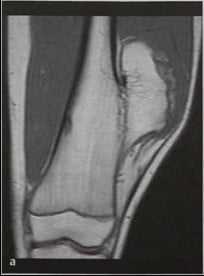

Остеохондрома (костно-хрящевой экзостоз бедренной кости ) Девочка 12 лет, визуализация дистальной части диафиза кости пораженного экзостозом. МРТ. Интенсивность сигнала сходна с жировой тканью на Т1-взвешенной последовательности (а).

Хрящевой колпачок, имеющий выраженную гиперинтенсивность, выявляется на изображении последовательности STIR с подавлением МР-сигнала от жировой ткани (b), и имеет наибольшую толщину 1,5 см. Экзостоз удален. Злокачественный процесс не обнаружен.